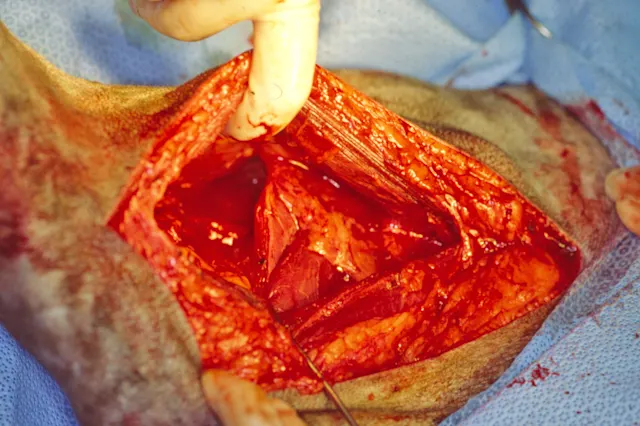

The Jackson-Pratt drainage system is commonly used in veterinary medicine. An alternative is to buy bulk rolls of silicone rubber tubing that can be cut to any length and sterilized. Fenestrations are cut into the distal end of the drain with scissors (Figure 1A); the drain is then attached to a Jackson-Pratt (grenade) reservoir that can be purchased separately. Large syringes can also be used as drainage reservoirs (Figure 1B). An 18-g or larger needle can be used to create a hole(s) along the plunger. The syringe can be attached to the drain. Negative pressure can be established by pulling back on the plunger, and the blunted needle can be placed through the hole(s) in the plunger to maintain the suction. Active drains for small wounds can be made using butterfly catheters and blood collection tubes (Figure 2). The reservoir can be emptied or the blood collection tubes can be replaced when more than half-full to maintain adequate suction. If the reservoir does not have a one-way valve, the tubing can be crimped when emptying it to prevent fluid in the drain tube from flowing retrograde back into the wound. Placement of an active drain after excision of a large intermuscular lipoma in the thigh of a dog is shown in Figure 3.

FIGURE 3A

Large intermuscular lipoma being excised from the thigh.